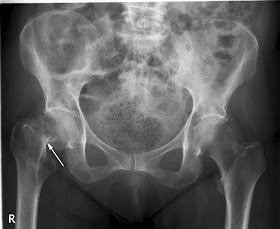

In this rather vivid news story the evidence is showing that hip fracture, while common and dangerous in seniors, has even more dire consequences in women around the age of 65.

"Fractures appeared to be most dangerous in the youngest segment of study participants: For women 65 to 69, hip fracture quintupled the odds of death within one year. This was also the only age group in which the odds of death remained higher in the fracture group after the one-year mark."

The least invasive methods to reduce the risk of hip fracture are a diet rich in Calcium and Vitamin D combined with weight bearing exercise. Heavy resistance exercise as recommended frequently by Reverse Magazine can do wonders to promote healthy aging and improve strength and mobility.